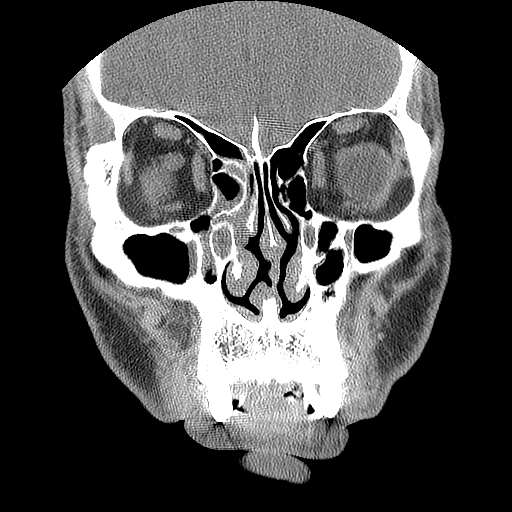

男,38岁,鼻塞、头痛2个月,要求鼻窦ct检查。

右侧上颌窦、蝶窦、筛窦、额窦及左侧上颌窦慢性炎症。

右侧鼻中隔左偏,右侧上颌窦、筛窦、额窦慢性炎性病变。右侧上颌窦开口粘膜增厚。

1)副鼻窦炎。2)右侧中鼻道及总鼻道粘膜息肉样变。3)双侧中下鼻甲肥大。4)鼻中隔轻度左突偏曲。